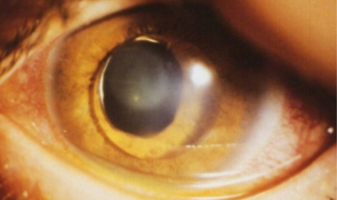

subluxation

subluxation (Marfan’s)

subluxation (Weill-Marchesani)